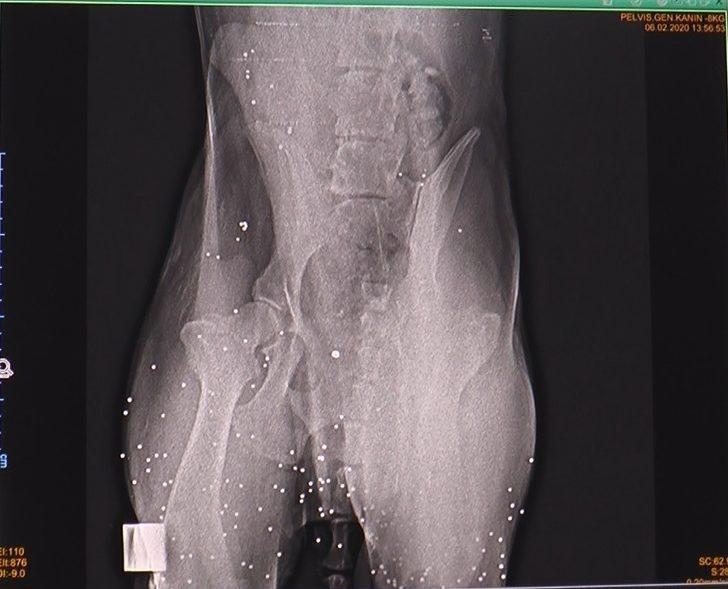

Nedenini bilmedikleri şekilde vatandaşların hayvanları vurduğunu ve ölümüne sebep olduklarını söyleyen Gültekin Atalan, “Kayseri’nin Hacılar ilçesinden geçen hafta sonunda bize ateşli silahla yaralama sonucunda getirilen sahipsiz bir köpeğin, yaptığımız tetkikler sonucunda vücudunun arka kısmına çok sayıda saçma isabet ettiğini belirledik. Hayvan geldiğinde genel durum bozukluğu mevcuttu ve hemen müdahaleyi yaparak gözetim altına aldık fakat maalesef vücuduna çok fazla saçma isabet ettiği için kurtaramadık. Yılda bize intikal eden hatırı sayılır ölçüde, ateşli silahla yaralamaya bağlı vakamız oluyor. Bunların neden gerçekleştiği konusunda tam bir bilgi sahibi olmamakla beraber, bu vakaların çoğunun şehir içinde olduğunu biliyoruz. Nedenini bilmediğimiz bu hareketler ile insanlar daha çok köpekleri yaralamaktadırlar ve ölümüne neden olmaktadırlar. Bu konunun da ayrıca ele alınarak, önlemlerinin alınması gerektiğini düşünüyoruz” dedi.